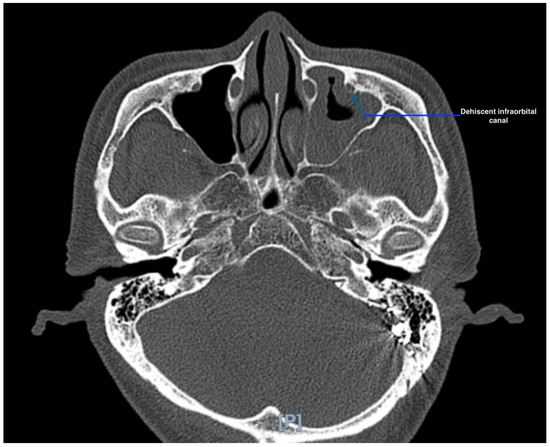

Background/Objectives: The sphenoid sinus (SS) exhibits marked morphological variability, influencing the relationship of critical neurovascular skull base structures. This study aimed to characterize sphenoid sinus pneumatization (SSP) patterns and assess their impact on the course of the internal carotid artery (ICA), optic [...] Read more.

Background/Objectives: The sphenoid sinus (SS) exhibits marked morphological variability, influencing the relationship of critical neurovascular skull base structures. This study aimed to characterize sphenoid sinus pneumatization (SSP) patterns and assess their impact on the course of the internal carotid artery (ICA), optic nerve (ON), Vidian nerve (VN), and maxillary nerve (MN) within a Greek adult population. Methods: A retrospective analysis of 253 adult skull base computed tomography (CT) scans was performed. The degree and direction of SSP were classified according to established radiological criteria. Anterior, lateral, and posterior extensions were evaluated. The course of adjacent neurovascular structures was categorized as typical, protruding, or dehiscent. Associations between pneumatization types and neurovascular variants were analyzed. Results: The sellar complete type was the predominant SS pattern (63.2%), followed by sellar incomplete (27.7%) and presellar (8.7%) types; agenesis was rare (0.4%). Posterior (63.6%) and lateral (46.6%) extensions were most common. Lateral and posterior pneumatization significantly correlated with protrusion and/or dehiscence of adjacent neurovascular structures, particularly the ICA, ON, and VN. LW extension was strongly associated with ON protrusion (96%), while PP and full-lateral extensions correlated with VN protrusion (56.1% and 79.9%, respectively). No significant sex- or side-related differences were identified. Conclusions: SSP demonstrates extensive morphological variability that significantly affects the anatomical course and osseous coverage of neighboring neurovascular structures. Comprehensive preoperative CT evaluation of SS anatomy is essential for planning endoscopic transsphenoidal and extended skull base procedures to minimize the risk of neurovascular injury. Full article

Show Figures

Figure 1